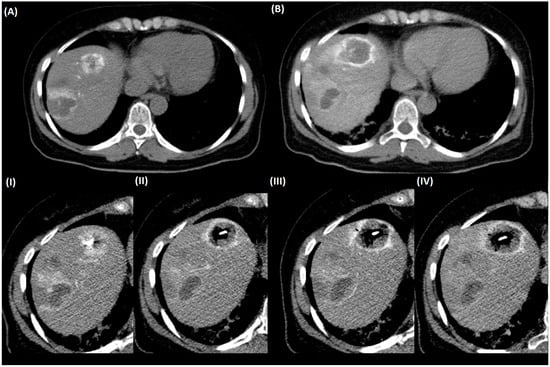

3.5. Periinterventional Control Scans for Needle Positioning

3.6. Post Ablation Control Scans

3.7. Outcome and Complication Rates